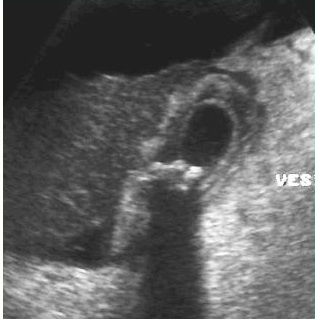

Image echographique de

cholecystite aigue lithiasique : Vesicule est

distendue , paroi epais , image de calcul

multiple au ventre de la vesicule biliaire |